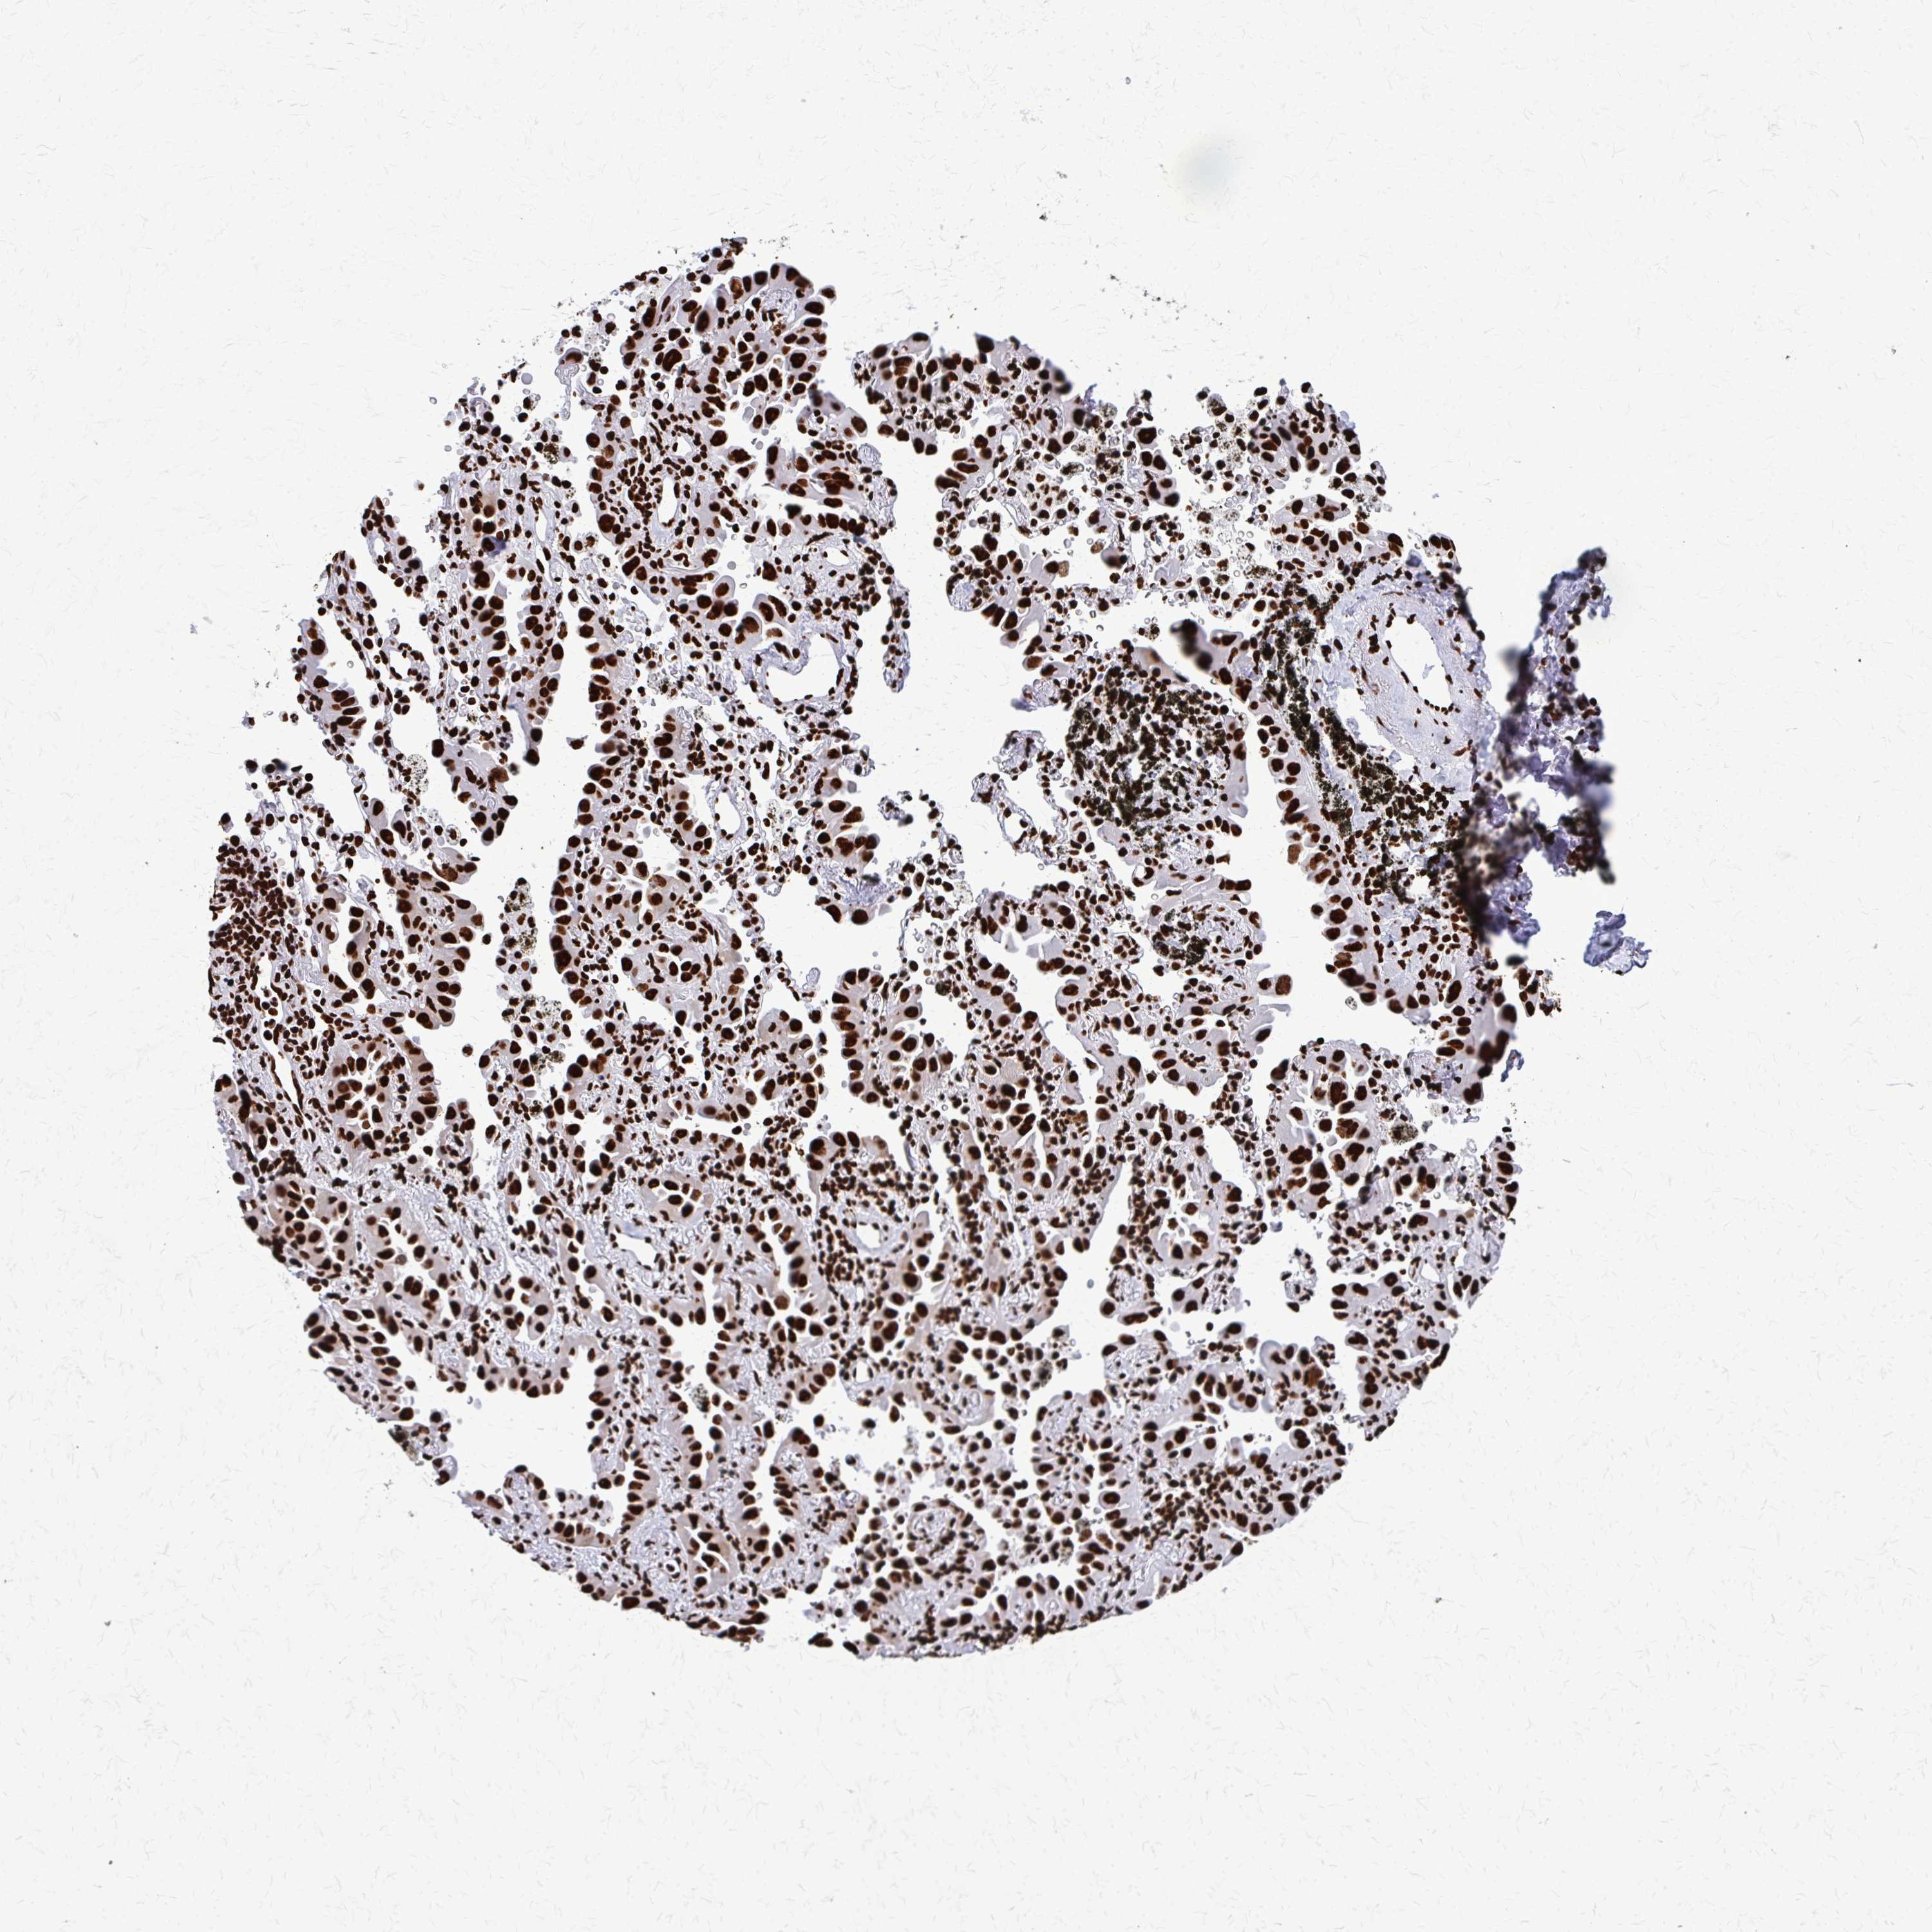

CANCER LUNG CANCER Show tissue menu

LUAD TCGA LUAD VALIDATION LUSC TCGA LUSC VALIDATION PROTEIN LUAD CPTAC PROTEIN LUSC CPTAC PROTEIN EXPRESSION